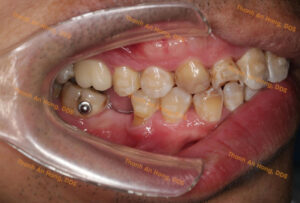

HÌNH ẢNH THỰC TẾ

Chỉnh khay dựng trục răng cối lớn hàm dưới